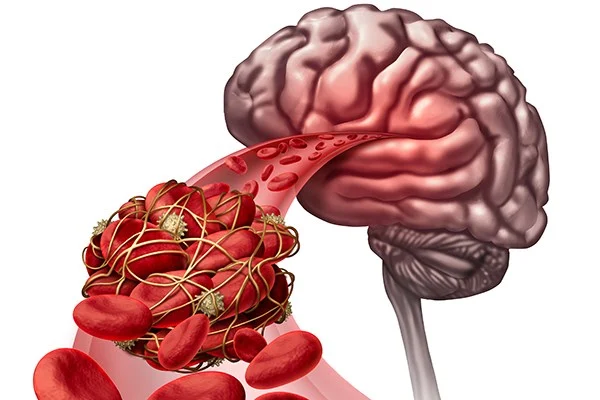

Mechanical thrombectomy is an emergency procedure for strokes caused by blocked brain arteries. It is performed when sudden weakness, speech difficulty, or paralysis occurs.

Special catheters remove the clot quickly, restoring blood flow, minimizing brain damage, and significantly improving recovery when done within the treatment window.